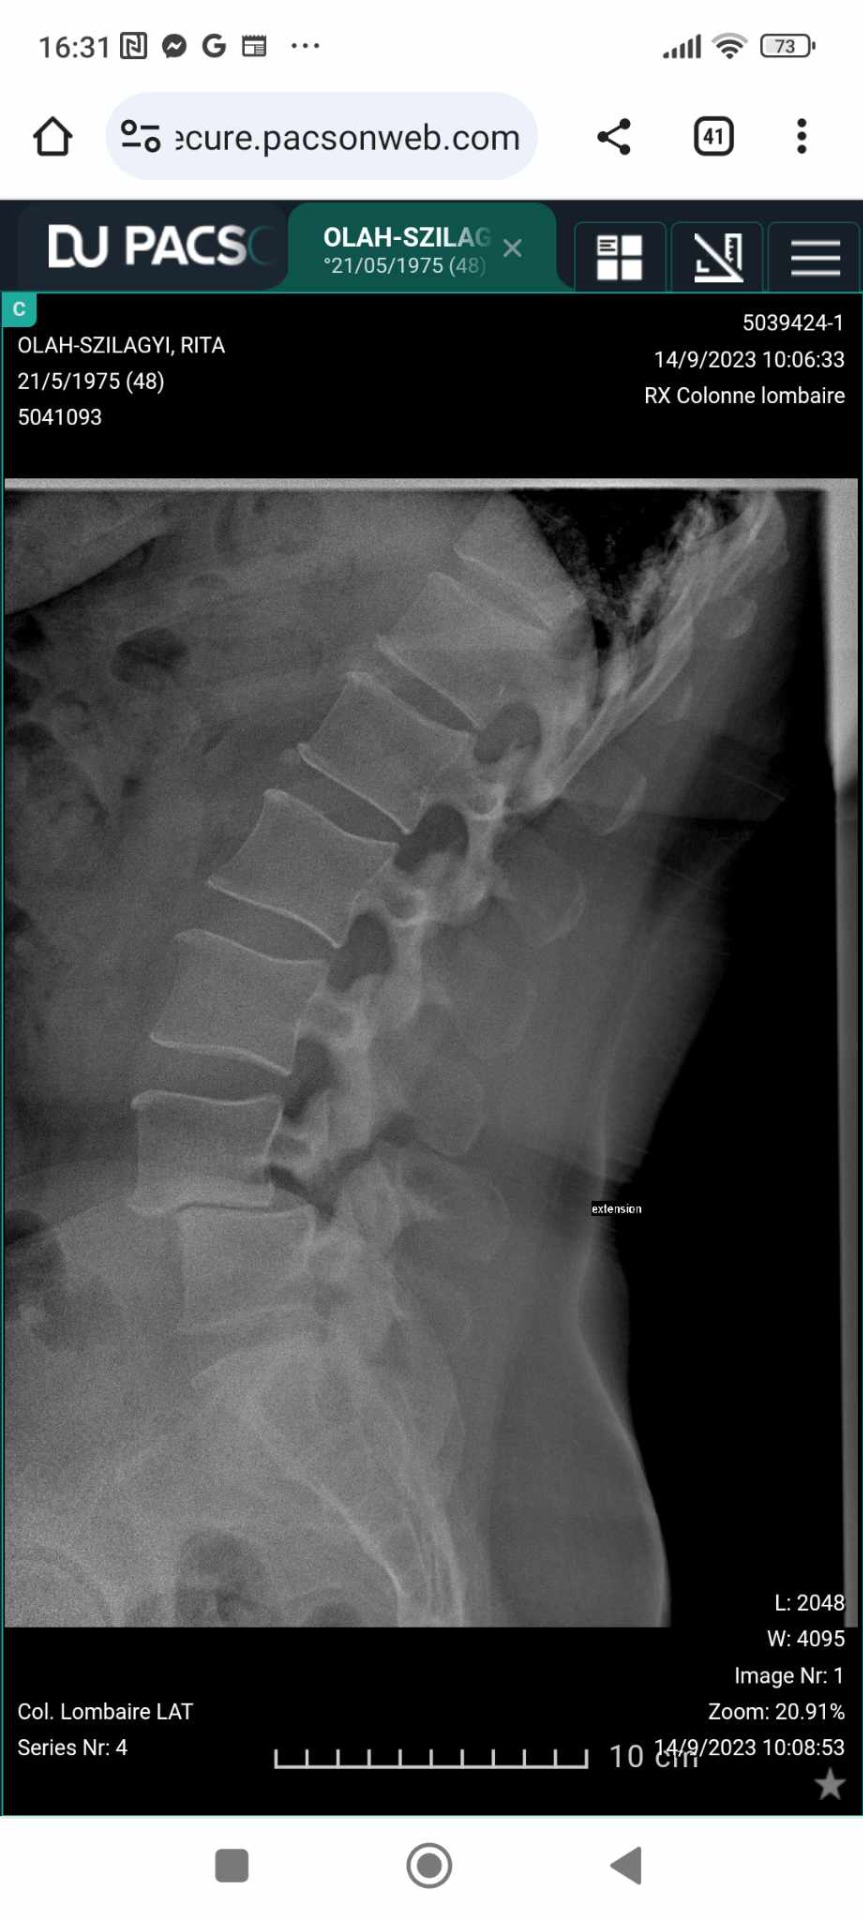

Az én esetemben sajnos gyógyulásról nem lehet szó, mert az elcsúszott, elmeszesedett, artritiszes (állandó gyulladásban lévő) csigolyáimat csak műtéti úton lehetne a helyükre visszatenni. Ezt egyelőre nem akarják az orvosok megtenni az ágyéki (L4-L5) csigolyáimnál, arra hivatkozva, hogy még túl fiatal vagyok. Tehát a kiné csak a fájdalom enyhítésében tudna segíteni, ha...

Legelőször akkor találkoztam kinével, amikor 2014-ben diagnosztizálták a betegségemet. Csigolyacsúszások a gerincemen 1 a nyaki részen (C5-C6) és egy az ágyéki részen (L4-L5). Akkor a neurológus úgy engedett haza a konzultációról, hogy döntsem el melyiket akarom először műttetni a nyakamat vagy az ágyéki részt, addig felírt 18 alkalom kinét.

Az én L4-es csigolyám már 8,5 mm-re van elcsúszva a hasfal felé, ül az L5-ös csigolyán. Nem gondolom, hogy bármilyen jól irányzott mozdulattal ezt vissza lehetne helyezni a helyére.

A megbeszélt találkozóra 40 perc késéssel megérkezett egy 23 éves lányka kiné. Elvette az orvosi beutalómat, biztosan nem olvasta el, mert annyi idő alatt nem lehet, és kezdtük a kezelést. Ő is egy székre ültetett, hozta a testápolóját és kezdett masszírozni. Felment az agyvizem. Hogy lehet széken ülve, ami az én hátamnak a legrosszabb pozíció, masszírozni? Amikor a lányom masszíroz fekve az ágyon szakértelem nélkül, az esküszöm hasznosabb. Ezt nevezik gyógymasszázsnak? Majd lefektetett a szőnyegre a hátamra és olyan feladatokat kezdett csináltatni, ami lehetetlennek tűnt. Nem tudok homorítani, még a röntgenen is probléma volt mikor kérték, hogy hajoljak hátrafelé a felvétel kedvéért. Közöltem vele, hogy ilyen jellegű gyakorlatokat már 8 éve nem csinálhatok. Azt kérdezte: - Miért? Mondtam azért, mert ezek tovább csúsztatják a csigolyáimat a rossz irányba. Látszott rajta, hogy nem érti az aggályaimat, én pedig meggyőződtem róla, hogy fogalma sincs arról mi a betegségem. Letöltöttem az Internetről a saját orvosi oldalamról a gerincemről készült MRI felvételeket és a következő alkalommal megmutattam neki. Elképedve nézte, mennyire deformált a gerincem. Leesett neki, miért mondtam az előző feladataira, hogy nem hasznosak.